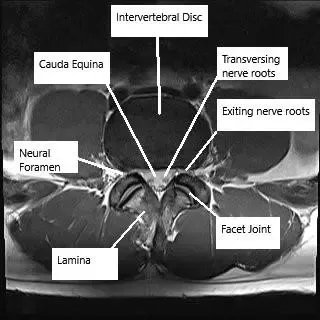

Resonancia magnética de la columna lumbar en corte axial y sagital

Resonancia magnética de la columna lumbar en corte axial y sagital.

Las radiografías proporcionan una visualización básica de la alineación de la columna vertebral y la integridad ósea. Los TAC ofrecen imágenes detalladas de las estructuras óseas y son útiles en traumatismos o afecciones degenerativas. La RM es la mejor herramienta de diagnóstico por imagen para evaluar los tejidos blandos, incluidos los discos intervertebrales, los ligamentos, las raíces nerviosas y la médula espinal.

La resonancia magnética también puede mostrar hernias discales, compresión nerviosa y cambios postoperatorios, como la colocación de una prótesis discal cervical, un implante que restablece el movimiento en un segmento vertebral enfermo.